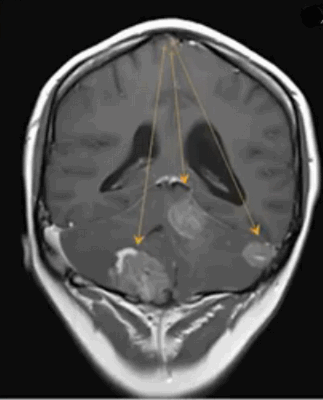

Эпендимома при МР-сканировании головного мозга

- эпендимомы — предположительно образуются в эмбриональном периоде. Характеризуются четкими контурами, плотнее, чем здоровые ткани, редко вызывают отек, чаще обнаруживаются в полостях желудочков;